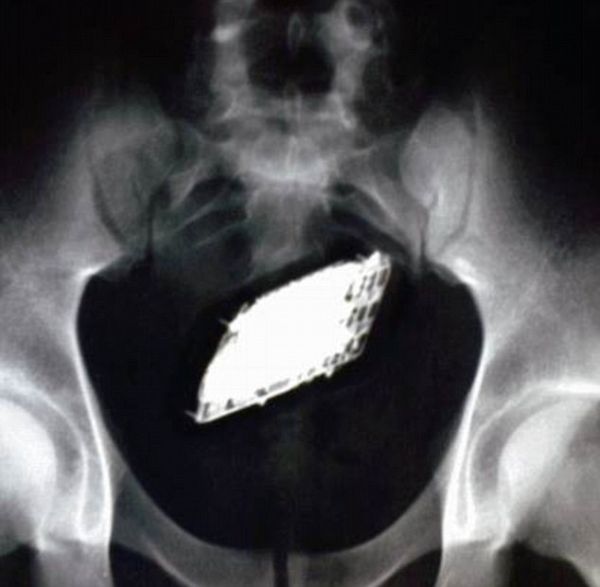

Подборка самых необычных способов спрятать мобильный телефон в тюрьме и другие креативные гаджеты, которыми они пользуются за решеткой каждый день. Интересно, как их все-таки вычислили? :)